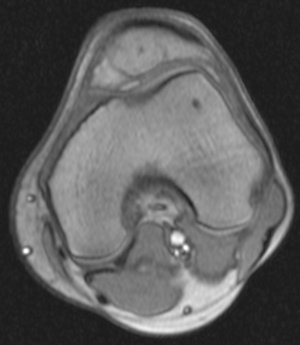

Недавно,5 сентября получил травму на работе. Выходя из транспорта почувствовал резкую боль с внутренней стороны колена (как бы ножом режет). Весь день не мог нормально поднять ногу. Особенно боль проявлялась при спуске по ступенькам. Через 3 часа после травмы обратился в травмпункт. Там сделали рентгенный снимок и сказали, что все впорядке. На следующий день весь коленный сустав с внешней стороны стал как бы после заморозки (холодить изнутри). Через дней 5-6 боль притупилась, а еще через несколько дней прошла. Но сустав все еще морозит изнутри. При резких движениях ощущения что кости сустава выходят и входят обратно на свое место. И сустав как будто чугунный. 8 октября сделал МРТ (так как большие очереди пришлось месяц прождать). Врач делавший МРТ сказал что дислокация коленной чашечки. К травмотологу только через неделю записан. Может подскажите что это? И последнее, сегодня начал морозить изнутри и сустав другой ноги. И холодок теперь идет от колена и вниз аж до пальцев на обеих ногах. Как бы онимения. Теперь не могу пробежать и нескольких метров такое ощущения что ниже колена мышцы как деревянные. Вот некоторые снимки МРТ. Рентген будет завтра на руках, если понадобится. Есть ли на самом деле смещение коленной чашечки?